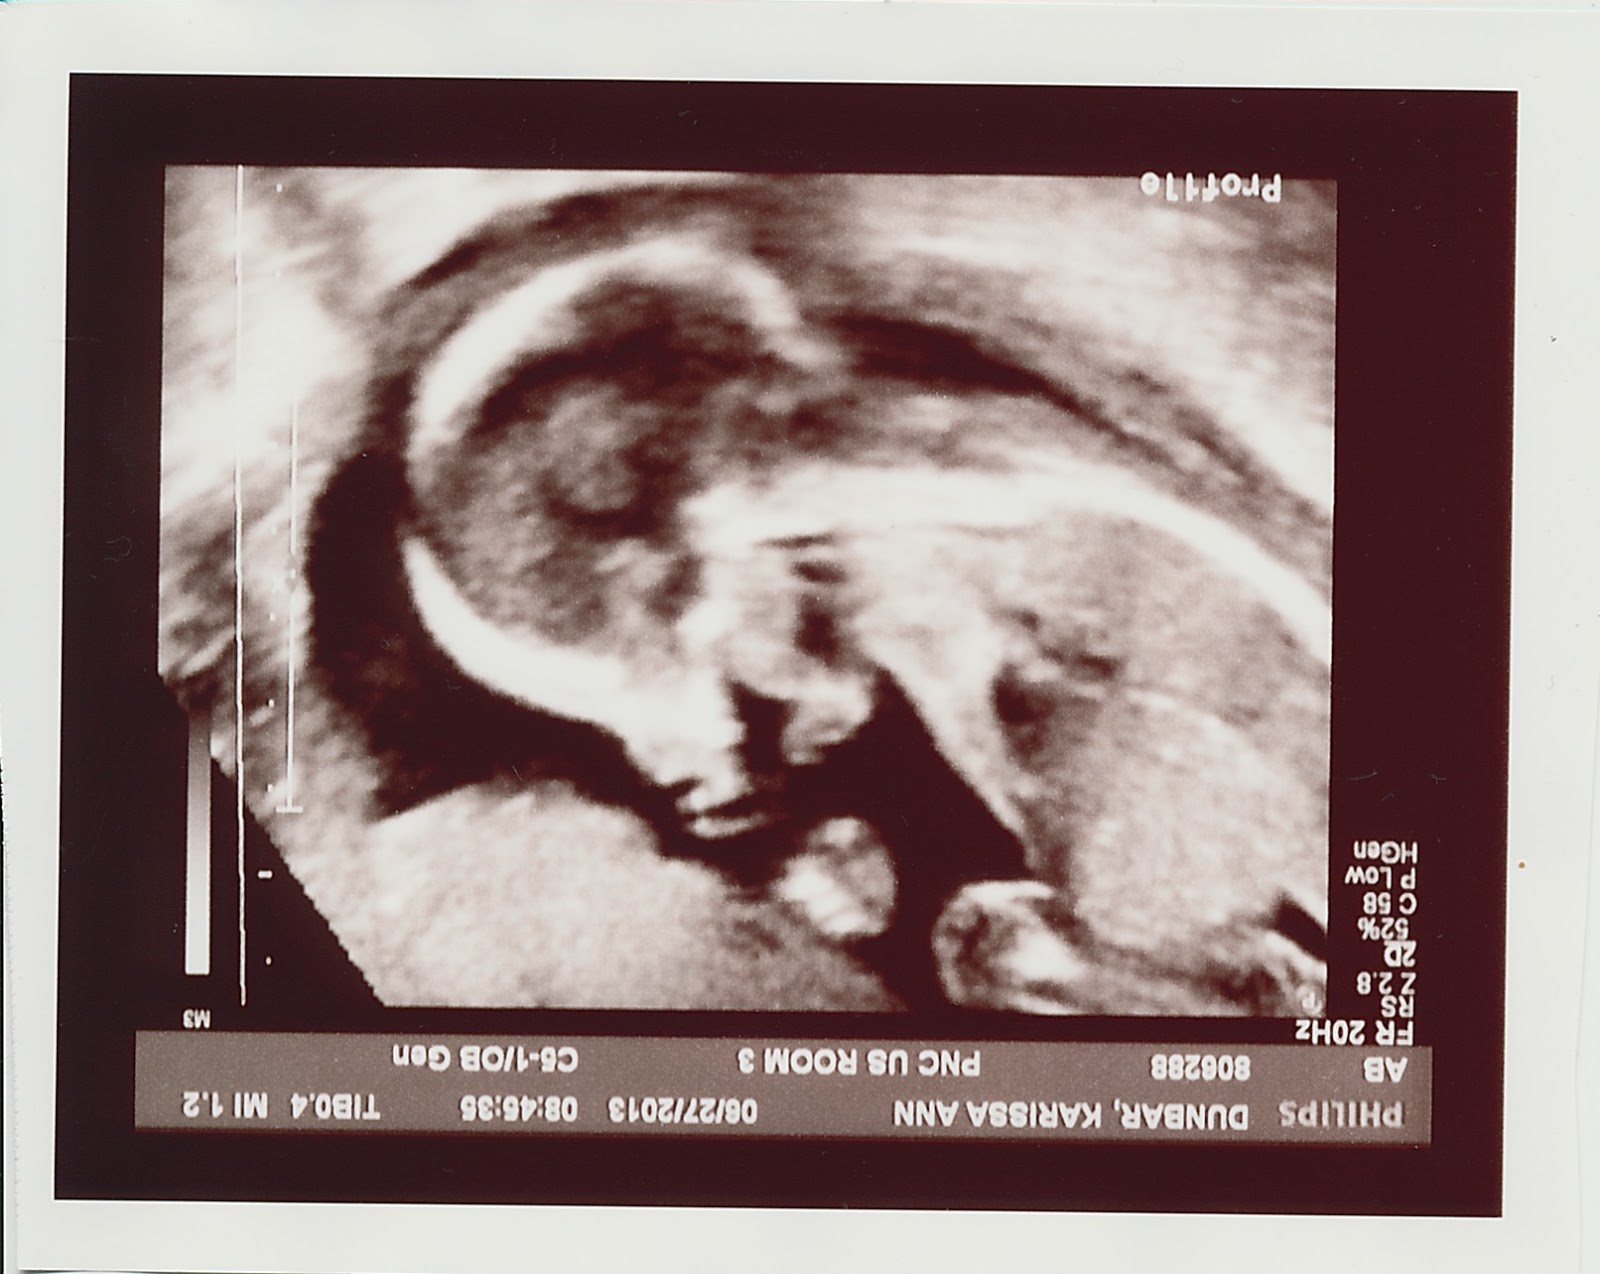

So the ultrasound-ologist also got some awesomely creepy baby photos… check these two out:

Predator baby!  Jason’s so proud.

Scary, right?  Haunted baby.